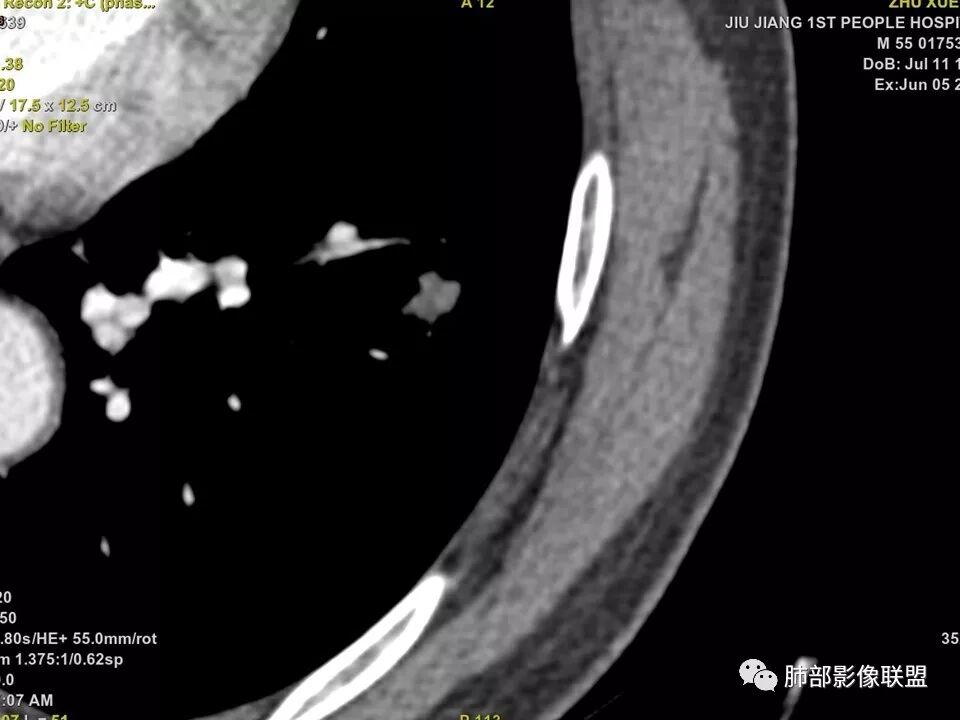

中年男性,左肺下叶不规则实性结节,有分叶及棘状凸起,支气管截断,轻度不均匀强化,考虑鳞癌,鉴别炎性肉芽肿。

左肺下叶前内基底段结节 深分叶和脐凹 表面部分膨隆 部分收缩 支气管截断 轻度强化 中央有坏死 考虑鳞癌 鉴别炎性结节

中年男性,支气管门口截断、邻近支气管未见管壁增厚,分叶明显,边缘彭隆,内见小坏死灶,周围未见GGO,考虑周围性鳞癌,鉴别炎性肉芽肿。

边缘有光滑,有圈黑晕,强化弱,似乎有脂肪密度,支气管截断的部位很自然,没有鼠尾状狭窄,考虑软骨型错构瘤?

这个支气管开口位置,如果是肿瘤应该有管壁浸润,也应该有膨胀感,这个没有,不像恶性肿瘤的支气管截断

病灶部分平直丶内收,有脂肪密度,不强化支持错构瘤。部分病灶有结节堆积感,分叶,与支气管、肺动脉关系密切,需鉴别腺癌。不强化进一步结核结节。

典型CT特征包括:(1)圆形或椭圆形边界清楚的病灶。(2)大小1~4cm,有轻微分叶改变。(3)较均匀的软组织影,多伴有钙化。(4)无毛刺,卫星灶及肺门或纵隔淋巴结肿大。(5)CT增强扫描无强化或轻度强化,其强化可能与软骨瘤间质中的薄壁血管或周围慢性炎症反应有关。